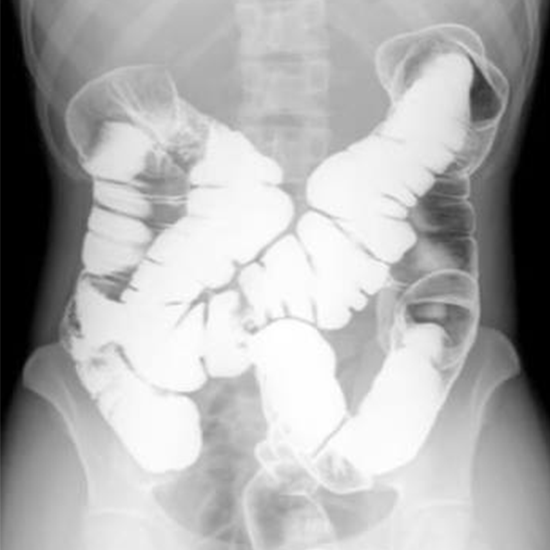

A barium enema is an X-ray imaging procedure used to examine the lower intestinal system. Symptoms including abdominal pain, bowel changes, and chronic diarrhea may lead your doctor to order this test.

• To diagnose blood in the stools and suspected colorectal cancer.

• • To determine the reason for any change in bowel habits.

• • To check for rectum obstructions.

• • To identify non-specific stomach pain.